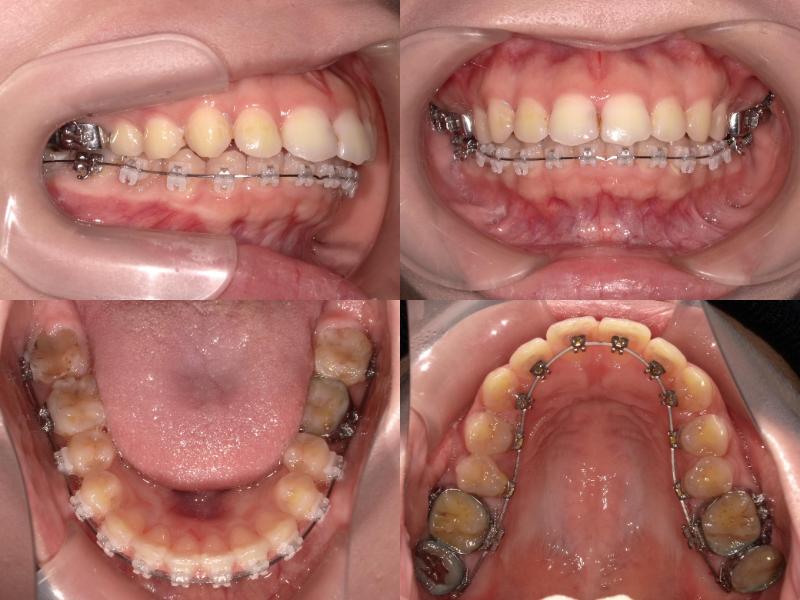

上下左右5番を抜歯し、上顎6番を口蓋正中縫合部からアンカースクリューで固定。

さらに、上顎2・3番の間に埋入したアンカースクリューから前歯を圧下し、口元の突出感とディープバイトの改善を図りました。

左上7番は再根管治療を行いできるだけ保存しましたが、矯正治療途中で症状が悪化したため抜歯となりました。

上顎6番を口蓋正中縫合部からアンカースクリューで固定し、さらに上顎2・3間に埋入したアンカースクリューから前歯を圧下しました。

この症例では、上顎前歯唇側にアンカースクリューを2本埋入し、上顎前歯の圧下を行うことでリスクをコントロールしました。